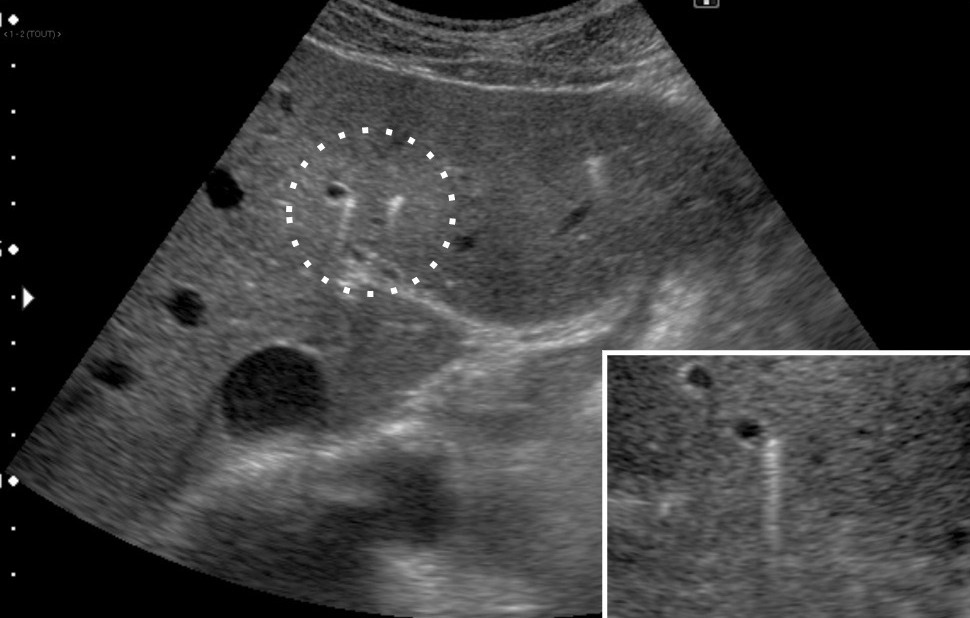

L’échographie hépatique est l’examen clé pour le diagnostic de syndrome LPAC. Celle-ci met typiquement en évidence les signes d’une microlithiase intrahépatique sous la forme d’images en « queue de comète » (échos de répétition liés à la vibration des microcristaux sous le faisceau d’ultrasons), de micro-­spots ou de « boue biliaire » (sludge) le long des canaux intrahépatiques (fig. 1A). Ces signes sont parfois difficilement identifiables, notamment en situation non sensibilisée et pour un opérateur non entraîné. Le principal diagnostic différentiel est représenté par les microhamartomes (ou complexes de von Meyenburg) qui peuvent parfois se présenter sous la forme d’artéfacts en queue de comète.9 Une échographie normale standard n’élimine pas le diag­nostic et il peut être nécessaire de répéter l’examen par un radiologue expérimenté et formé à la sémio­logie du syndrome LPAC. Moins fréquemment (5 à 10 % des cas), le syndrome LPAC peut se présenter sous la forme de vrais calculs (macrolithiases) intra- ou extrahépatiques (fig. 1B).4 Une lithiase vésiculaire n’est observée que chez un tiers des patients atteints de syndrome LPAC.

La cholangiographie par IRM est typiquement normale dans les formes habituelles, microlithiasiques, du syndrome LPAC. Elle n’est donc pas nécessaire au diagnostic dans la très grande majorité des situations. Elle doit être réalisée en cas de calculs intrahépatiques ou de dilatation des canaux biliaires en échographie afin d’évaluer le retentissement de ces calculs sur les voies biliaires et le parenchyme hépatique. Les calculs biliaires ne sont pas toujours visibles à l’imagerie par résonance magnétique (IRM), notamment quand leur taille est inférieure à 5 mm. Lorsqu’ils sont visibles, ils sont le plus souvent visualisés en hyposignal T1 et T2 sous forme de lacunes endobiliaires (fig. 2 A et 2B). Dans une série récente portant sur 125 patients suivis dans un centre expert et ayant tous eu une bili-IRM, 49 % présentaient des anomalies des canaux biliaires, parmi lesquelles 93 % de calculs intra­hépatiques et 38 % de dilatation des canaux biliaires.10 Ces anomalies morphologiques étaient plus fréquemment observées chez les porteurs d’un variant pathogène du gène ABCB4.